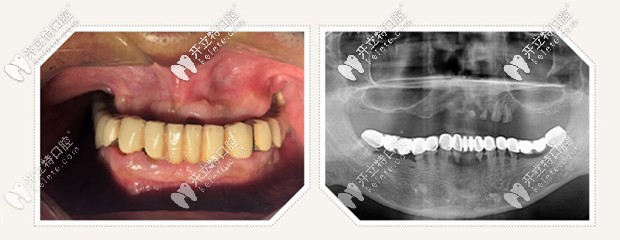

老爸已經(jīng)50多歲了,隨著年齡的逐漸增長,這牙齒也在慢慢“罷工”,之前老爸戴的是活動假牙,但是時間一長,上半口假牙總是掉,每次吃飯的時候,我看著都是難受。

由于爸爸長期戴活動假牙,上半口牙齒的咀嚼功能受損厲害,不僅想想大大折扣,而且在日常的社交生活中也有很多的不方便啊!

但是經(jīng)過拍片檢查,醫(yī)生說老爸的頜骨情況良好,可以進(jìn)行即刻種植,為了保證植體植入的準(zhǔn)確性,醫(yī)生給的治療方案是采用數(shù)字化導(dǎo)板微創(chuàng)精準(zhǔn)植入,同時較少了傳統(tǒng)翻瓣手術(shù)的痛苦。

all on 4即刻種植,只需要植入4顆種植體,就把老爸上半口牙就全給修復(fù)啦,并且是當(dāng)天修復(fù),當(dāng)天戴牙啊,感覺太神奇啦!